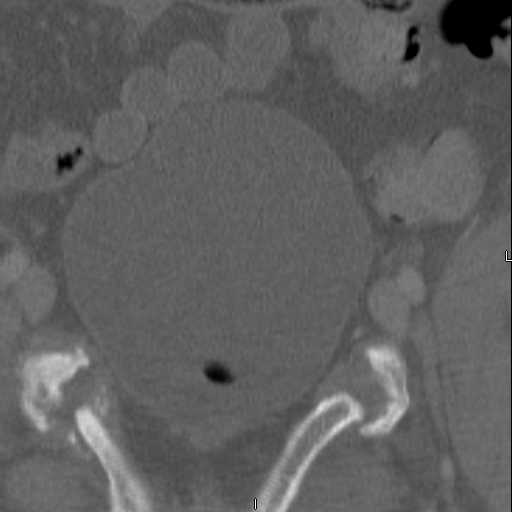

Here are a recent patient’s example slides...

54 yo Female Fell c/o Pain

3 Months After Fall

Continued Pain & Immobility

(+) Instability to Compressive Manual Exam

Pelvic CT Scan - 3 Months After Fall

Sacral Injuries

Ramus Fractures

Percutaneous Fixation

(B) Ramus-Retrograde

2 TransIliac-TransSacral

Upper Segment